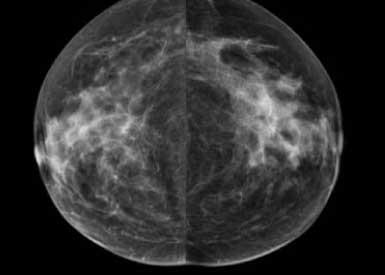

Recent studies have found that dense breast tissue is a strong independent risk factor for breast cancer. Breasts are composed of fat and fibroglandular tissue. Dense breast fibroglandular tissue appears white on a mammogram. Abnormalities and tumors also appear white on mammograms, causing them to be difficult to spot in dense breasts until the cancers are much larger and possibly in advanced stages.